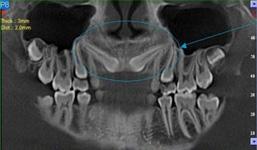

Je speciální zubní digitální tříprostorový tomograf (3D), který umožňuje na základě jediného

snímkování vytvořit všechny typy RTG zobrazení, které jsou pro lékaře potřebné. Díky používané technologii tzv. „kuželového paprsku“ a speciálním senzorům je

výrazně zmenšená dávka záření - o více jak 80% proti klasickému CT vyšetření. To je významné zejména u dětí. Pomocí tohoto přístroje je možné zjisti skutečnou situaci v čelistních kostech pacienta tedy množství kosti - můžeme změřit skutečnou šířku i výšku kosti, i kvalitu kosti (hustotu) v místě uvažované implantace. 3D (tříprostorové) zobrazení umožňuje zvýšit prostorovou představu operatéra ještě před vlastní operací a zároveň pacientovi lépe objasnit a ukázat oblast plánovaného zavedení implantátu.

Pacient „neumí číst“ RTG snímky, ale díky 3D zobrazení vidí „svoji skutečnou čelist“

- např. jak je nízká či úzká, vidí průběh nervu nebo velikost čelistní dutiny, což mu umožní i pochopení nutnosti v některých případech provést pomocné zákroky ještě před vlastním zavedením implantátu (viz. kostní štěp, sinus lift, kostní granulát...).

Vyšetření pomocí tohoto přístroje používáme i ve stomatochirurgii (zlomeniny čelistí, zuby moudrosti, cysty, onemocnění čelistního kloubu), ortodoncii (retinované zuby, nadpočetné zuby), parodontologii atd.